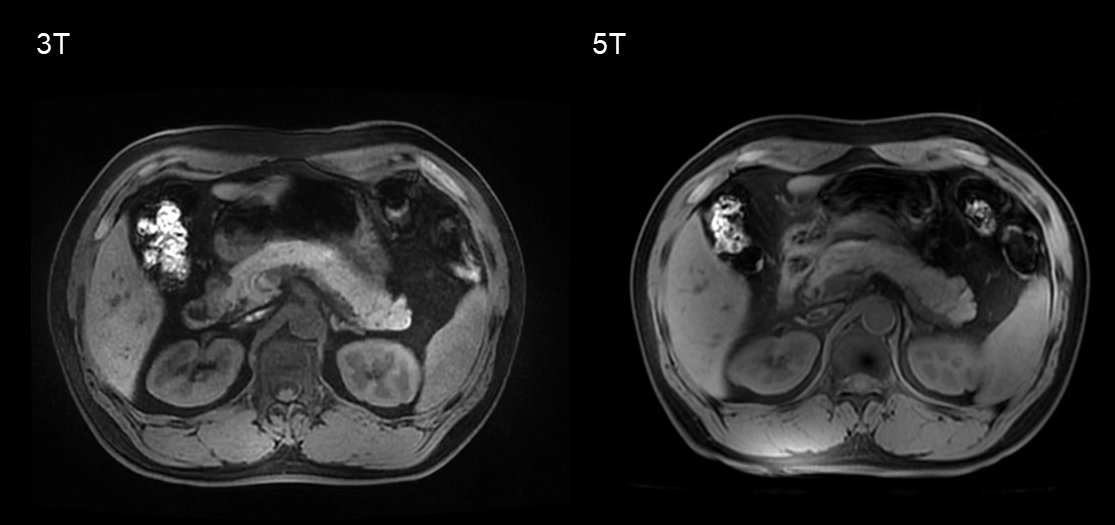

Figure 1-3 shows an example of 5T MRI and 3T MRI for each sequence. Interobserver agreement in image quality and artifacts was substantial to excellent for all sequences (κ > 0.7). Compared to the 3T examination, T1-weighted and DWI sequence at 5T showed significantly better image quality and comparable artifacts. For T2-weighted images, there was no significant difference in image quality ratings and the presence of artifacts between 3T and 5T. The mean ratios of SNR at 5 T to 3T of the T1-weighted images for the pancreatic head, body, and tail were 1.45, 1.35, and 1.48, respectively. For T2-weighted images, the corresponding ratios were 1.16, 1.33, and 1.39, respectively. For the DWI images (b = 800 s/mm2), the corresponding ratios were 1.29, 1.40, and 1.24, respectively. The SNRs of all the sequences were significantly higher at 5T than at 3T (P < 0.05 for all comparisons). For both 3T and 5T, mean ADC values on the pancreatic head were significantly higher than those of the tail (P = 0.016 for 3T, and P = 0.018 for 5T), while no significant difference was observed between the pancreatic head and body (P = 0.679 for 3T, and P = 0.445 for 5T). There was no significant difference in mean ADC values and CV of ADC between 3T and 5T (P > 0.05 for all comparisons).

Figure 1. T1-weighted gradient echo sequence at 3T and 5T from the same participant.